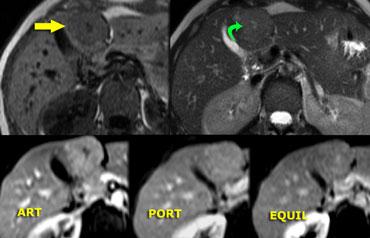

Bên trái là hình ảnh u máu điển hình.

Ngấm thuốc trong pha động mạch gần như đồng tỷ trọng với động mạch chủ, và khi thuốc cản quang khuếch tán về phía trung tâm tổn thương, mức độ ngấm thuốc giảm dần, và trong pha muộn vẫn còn tăng tỷ trọng so với các khoang mạch máu.

‘Ngấm thuốc mao mạch’ trong FNH. Lưu ý ngấm thuốc sớm nhưng không sáng bằng u máu. Trong pha tĩnh mạch và pha muộn, ngấm thuốc gần như đồng tỷ trọng với gan.

Cùng ca bệnh trên MR động học.

Lưu ý cách MR thể hiện rõ kiểu ngấm thuốc ngoại vi dạng nốt, lan dần vào trung tâm (mũi tên cong màu xanh) mà CT không thể hiện được.